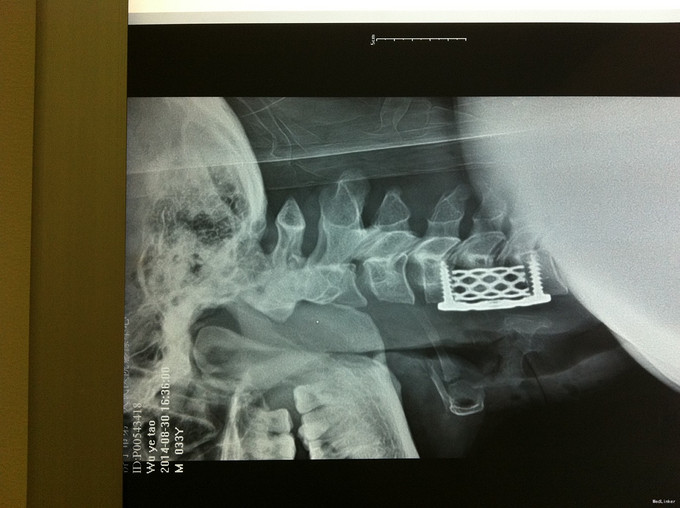

诊断:脊髓型颈椎病 处理: 1、完善相关辅助检查,明确诊断,有无手术指证; 2、全麻下行颈椎前路减压,颈椎间盘突出并骨赘形成,行颈6椎体次全切,减压较充分。

随访 1、应常规术后1个月、3个月、半年随访; 2、术后1个月,双下肢肌张力减低,行走不稳较前改善,继续服用营养神经药物。 讨论:1、颈椎病颈椎手术前路减压,两个节段椎间融合内固定术还是椎体次全切术?